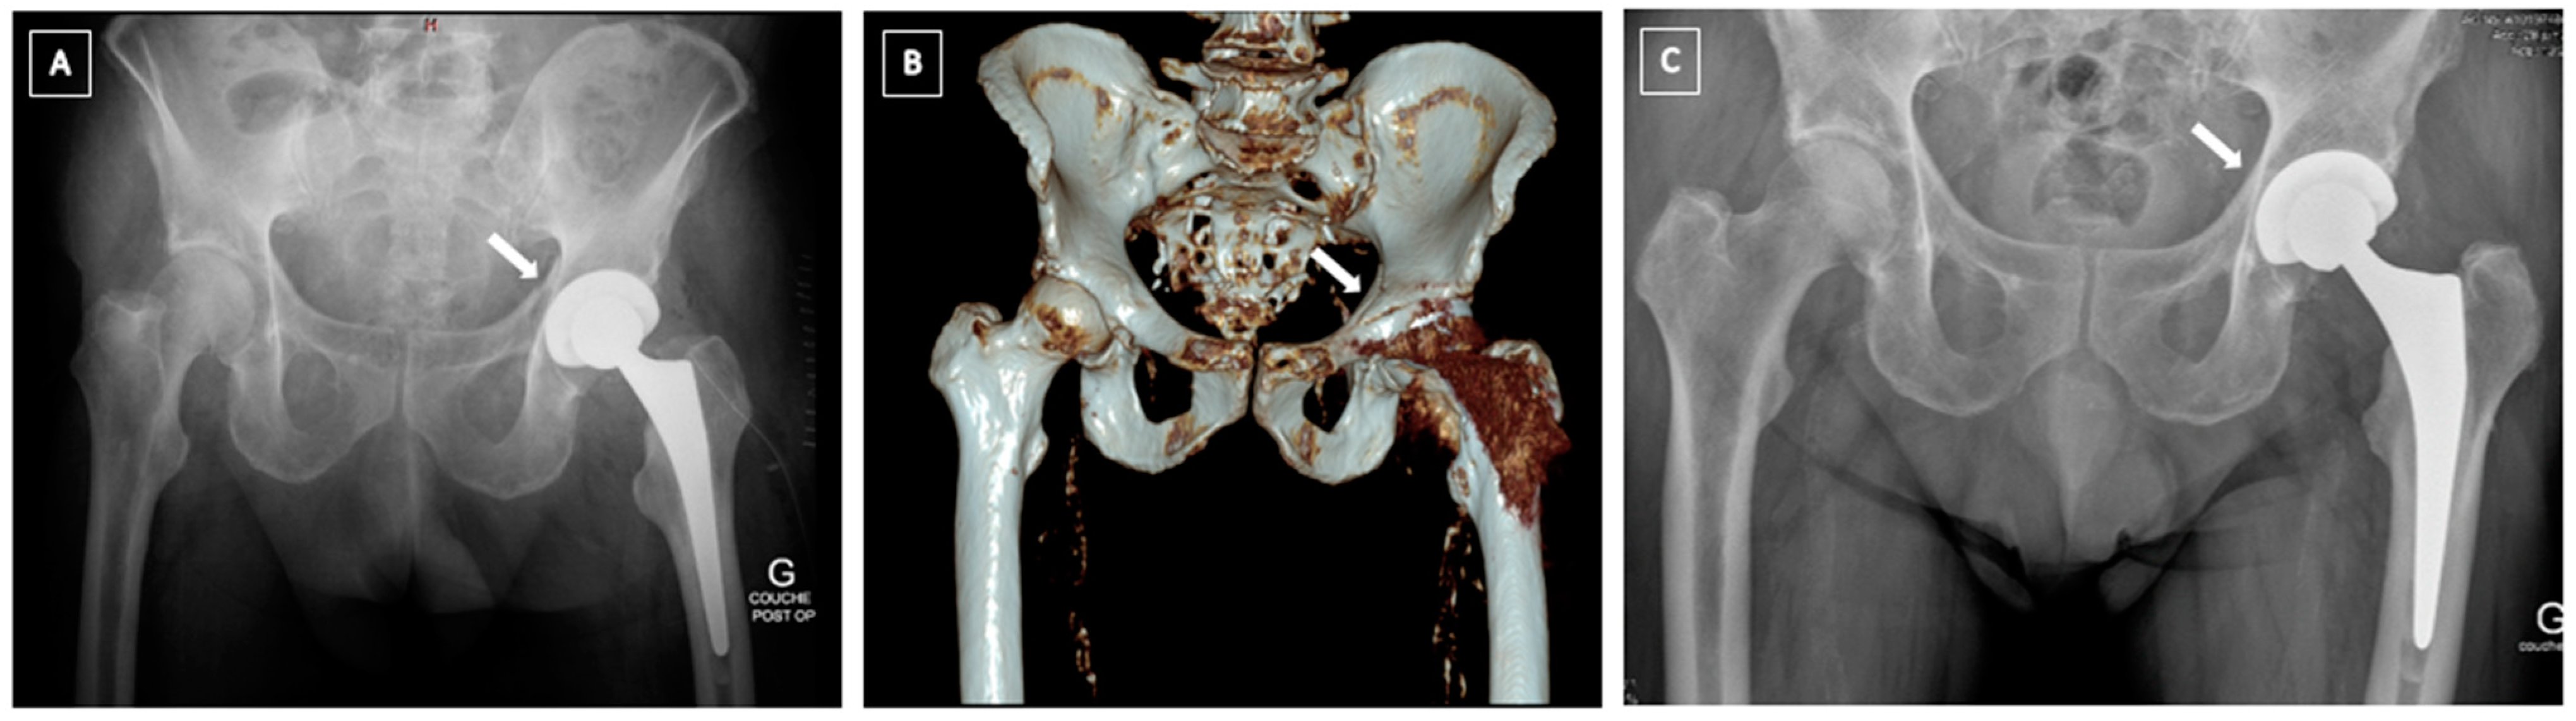

4.2. Post-Operative Fractures

4.3. Pelvic Discontinuity (PD)